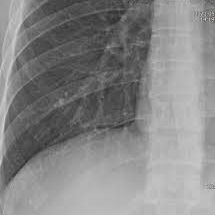

- 흉부 X-ray: 기본적으로 갈비뼈 골절 여부 확인 시 가장 많이 활용됩니다.

- CT(컴퓨터 단층 촬영): X-ray에서 확인이 어려운 미세골절, 연골 손상, 내부 출혈까지 파악 가능.